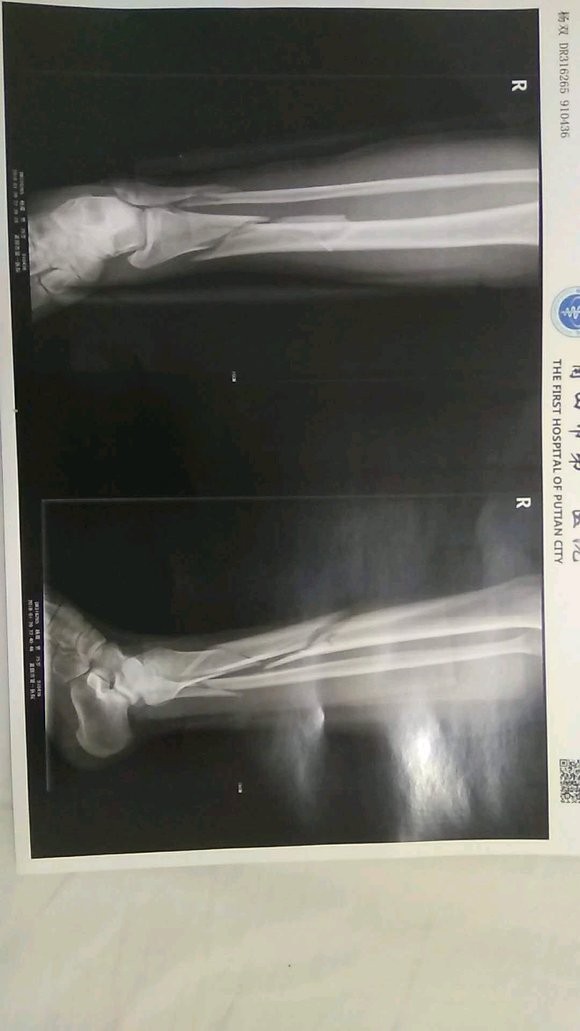

今天出车祸了,我这是骨折还是断了,以后在也不撸管了

断了

不知道楼上在瞎掰什么东西,粉碎性骨折要截肢我也是头一次听说。

楼主放心吧,手术后不要再撸管了。肾主骨,你要是还撸,一瘸一拐你不希望吧?!好好学习戒色文章吧,然后落实其中的内容,加油!!!